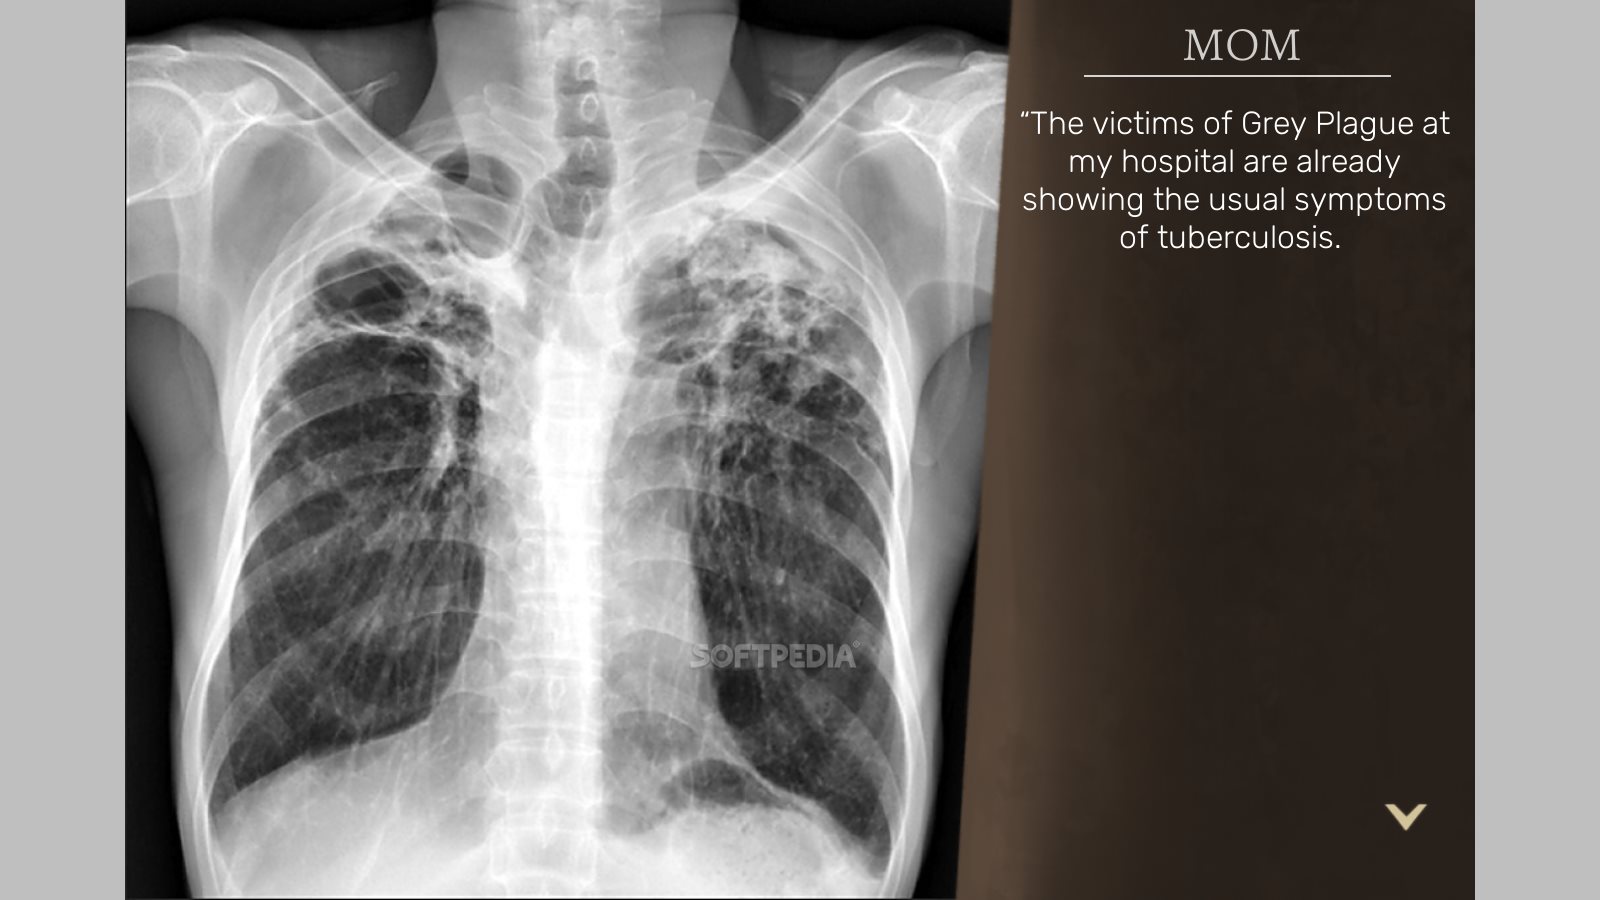

Поражение легких является одним из основных симптомов коронавируса (COVID-19). В данной статье представлены фото рентгеновских снимков, которые позволяют визуально оценить состояние легких при этом заболевании.

Фото рентгеновских снимков поражения легких при COVID-19

На фотографиях рентгеновских снимков видно, как вирус воздействует на легочную ткань. Характерные признаки поражения легких включают пятна, инфильтраты и наличие жидкости внутри легочных альвеол.

Фото рентгеновских снимков помогают врачам и специалистам визуально определить степень поражения легких и принять соответствующие меры лечения и поддержки пациента.